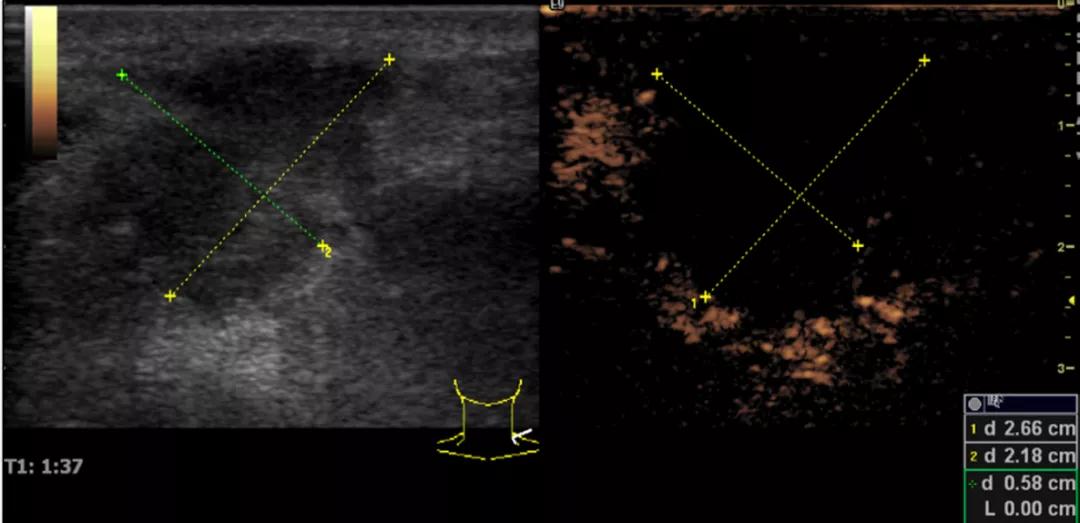

第三例是甲状腺癌患者,双侧甲状腺癌切除术后、碘治疗后一年余效果欠佳,超声显示左颈3区3枚低回声结节,穿刺示甲状腺乳头状癌转移。患者不愿意手术,希望采取局部治疗。对病灶进行液体隔离后采取热消融术,由于淋巴结较小,热消融一分钟左右完全灭活,术后增强影像显示没有脏器充填。

(病例3图例)